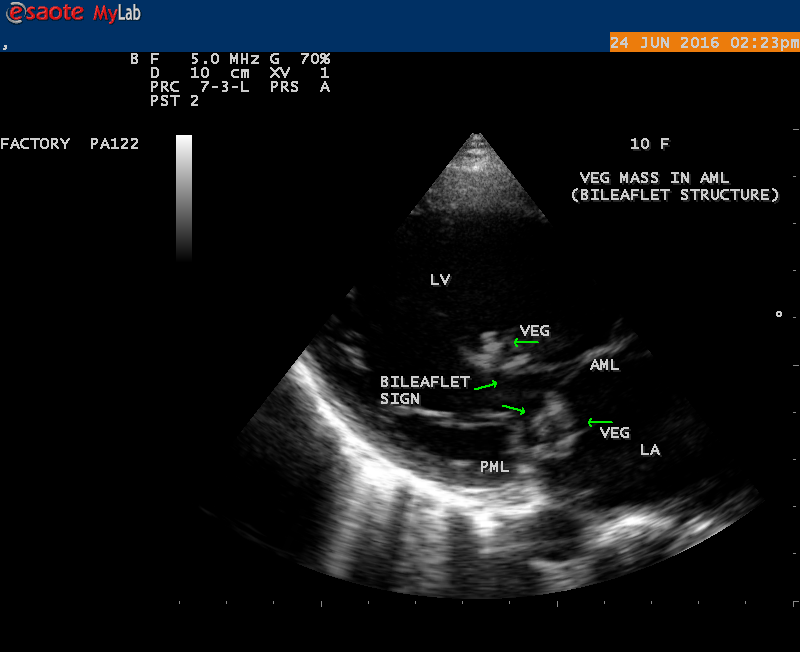

A 10 year female child was referred for echocardiographic evaluation with an apical systolic murmur. The child was having recurrent episodes of rheumatic fever (febrile illness with joint pains) at the age of 5-6 years and taken some treatment from the local medical practitioner, but she was not taken penicillin prophylaxis earlier. The child was remained afebrile for long period and no precipitating factors of infective endocarditis such as dental or genitourinary procedures in the past. General examination revealed normal growth and development, no cyanosis and clubbing and peripheral signs of infective endocarditis such s Osler’s nodes, Janeway lesions, Roths spots and splinter haemorrhages are not present and they are relatively rare in children. Physical examination revealed a grade 3/6 , blowing, high pitched, holosystolic murmur with a constant intensity and duration on dynamic auscultation and loudest at the apex with a radiation to left axilla and transmitted to the left infrascapular area and vertebral coloumn and it is due to the flow generating the murmur is directed posterolaterally within the left atrial cavity, suggesting the murmur of mitral regurgitation due to the rupture of chordae tendineae of anterior mitral leaflet. Blood culture revealed normal. Blood chemistry revealed the positive serum ASO titer, suggesting a recent streptococcal infection and other parameters are normal. X- ray chest reveled moderate cardiomegaly and ECG revealed a left ventricular volume overload pattern of eccentric hypertrophy due to LV dilatation as a result of severe mitral regurgitation and a normal rhythm. Transthoracic echocardiography revealed a giant vegetation ‘popcorn’ like in Figures 1,3 and 4 and ‘cucumber’ like in Figure 2, mainly attached to base and apical portion of anterior mitral leaflet as shown in Figure 31 and manifested in various size and shapes as shown in Figures 1 to 33. A flail anterior leaflet with a disorganized mitral regurgitation jet as shown in Figure 16 and 21 and the posterior leaflet is embedded with vegetation and resulting in ‘kissing forms’ as shown in Figures 13, 14 and 15 in echocardiography imaging. Tricuspid valve is also thickened and calcified as shown in Figure 2 in addition to thickened and calcified mitral leaflets, suggesting an underlying rheumatic etiology predisposing to the formation of vegetation. The child was given 1.2 million units of intramuscular benzathine penicillin injection as a therapeutic and initial prophylaxis dose for rheumatic fever and advised every 3 weeks for life long. Small doses of digoxin and diuretics are also prescribed and advised early surgery (mitral valve replacement) Transthoracic 2D images are as in Figures 1 to 33 are given below

The most common and direct evidence of infective endocarditis is the vegetation and it begins as a microscopic focus of infection and gradually grows into a conspicuous mass. It is typically an irregularly shaped, highly mobile, echogenic mass attached to the free edge of a valve leaflet ( most commonly at the coaptation line) and tends to develop on the ‘upstream’ side of the valve leaflets ( ie, the ventricular side of aortic valve and the atrial side of mitral and tricuspid valves. They may be seesile or pedunculated, but usually has an oscillating or fluttering motion, a typical feature of most vegetations. Vegetation move with the leaflet in a more chaotic (‘oscillating’) manner and it may prolapse through the valve into the LV (left ventricle) as it opens as shown in Figures 3, 4 and 16 and into LA (left atrium) as it closing (Figure 5 and 6) . The mass of vegetation is typically homogeneous with echogenicity similar to that of the myocardium. The infectious process often alter the valvular structure and function. Extensive involvement of the leaflet may result in chordal rupture, leading to severe regurgitation as shown in Figure 21 . Direct and typical signs of RMCT (ruptured mitral chordate tendineae) were chain-flail or whiplash-like changes and had an incidence of 86.7%, causing severe regurgitation and mitral chordal rupture is the leading cause of flail mitral leaflet[30]. A large vegetation may obstruct the valve orifice as shown in Figure 1 and 2 , sometimes termed as “obstructive-type bacterial endocarditis” and producing a functional valve stenosis ( Ping-Pong mitral stenosis [31]) similar to left atrial myxoma as shown in Figure 29.

The size and shape of vegetation vary due to curling of vegetation. The size of vegetation in this child is 35.6 x 9.3 mm as in Figure 17 , 20 x 23.7 mm as in Figure 1 , 32.9 x 13.9 mm as in Figure 2 .

The shape of vegetation varies in this child as ‘popcorn’ like (Figures 1,3 and 4 ), rod-shaped (Figure ), basket shaped (Figure 7 )[33-Figure 13.3], ‘baby in hand’ appearance (Figure 18), ‘cucumber shaped (Figure 2 ) and a ‘bunch of plantain’appearance (Figure 33 ), ring shaped (Figure 19 }, bileaflet structure (Figure 9 )with bileaflet MR jet as shown in Figure 10 . and kissing forms (Figure 13 - parasternal long axis view, Figure 14 - apical four chamber view and Figure 15 - short axis view)